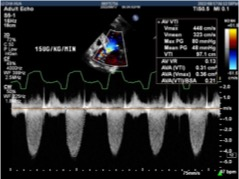

患者,80岁女性,因“反复气紧14年,加重20天”入院。曾于2015年行永久起搏器置入术,合并高血压。STS评分11.878%,虚弱体质。入院超声提示“主动脉瓣中重度狭窄”、“三尖瓣中度反流”。左室舒末径52mm,射血分值35%,主动脉瓣峰值流速3.64m/s,平均压差34mmHg。

行多巴酚丁胺负荷超声后,EF值提升至41.6%,主动脉瓣峰值流速4.48m/s,平均跨瓣压差48mmHg,诊断重度主动脉瓣狭窄。

即刻超声未见瓣周漏,主动脉瓣峰值流速1.5m/s,平均压差4mmHg